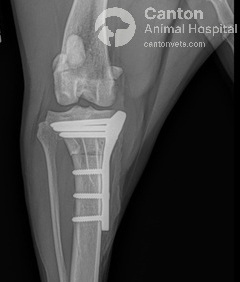

The proximal tibia (top of the shinbone) is carefully cut and rotated to change the slope of the tibial plateau.

A specialized bone plate is used to stabilize the osteotomy, ensuring proper healing.

Bone fragments are compressed and secured using a TPLO plate and screws, made of

surgical-grade stainless steel.

TPLO Implants and Fixation

Different types of bone plates and screws are used to stabilize the tibia post-surgery. At our hospital, we use the TPLO Locking System (Plate and Screws) from DePuy Synthes Vet, which ensures maximum strength and stability during healing.